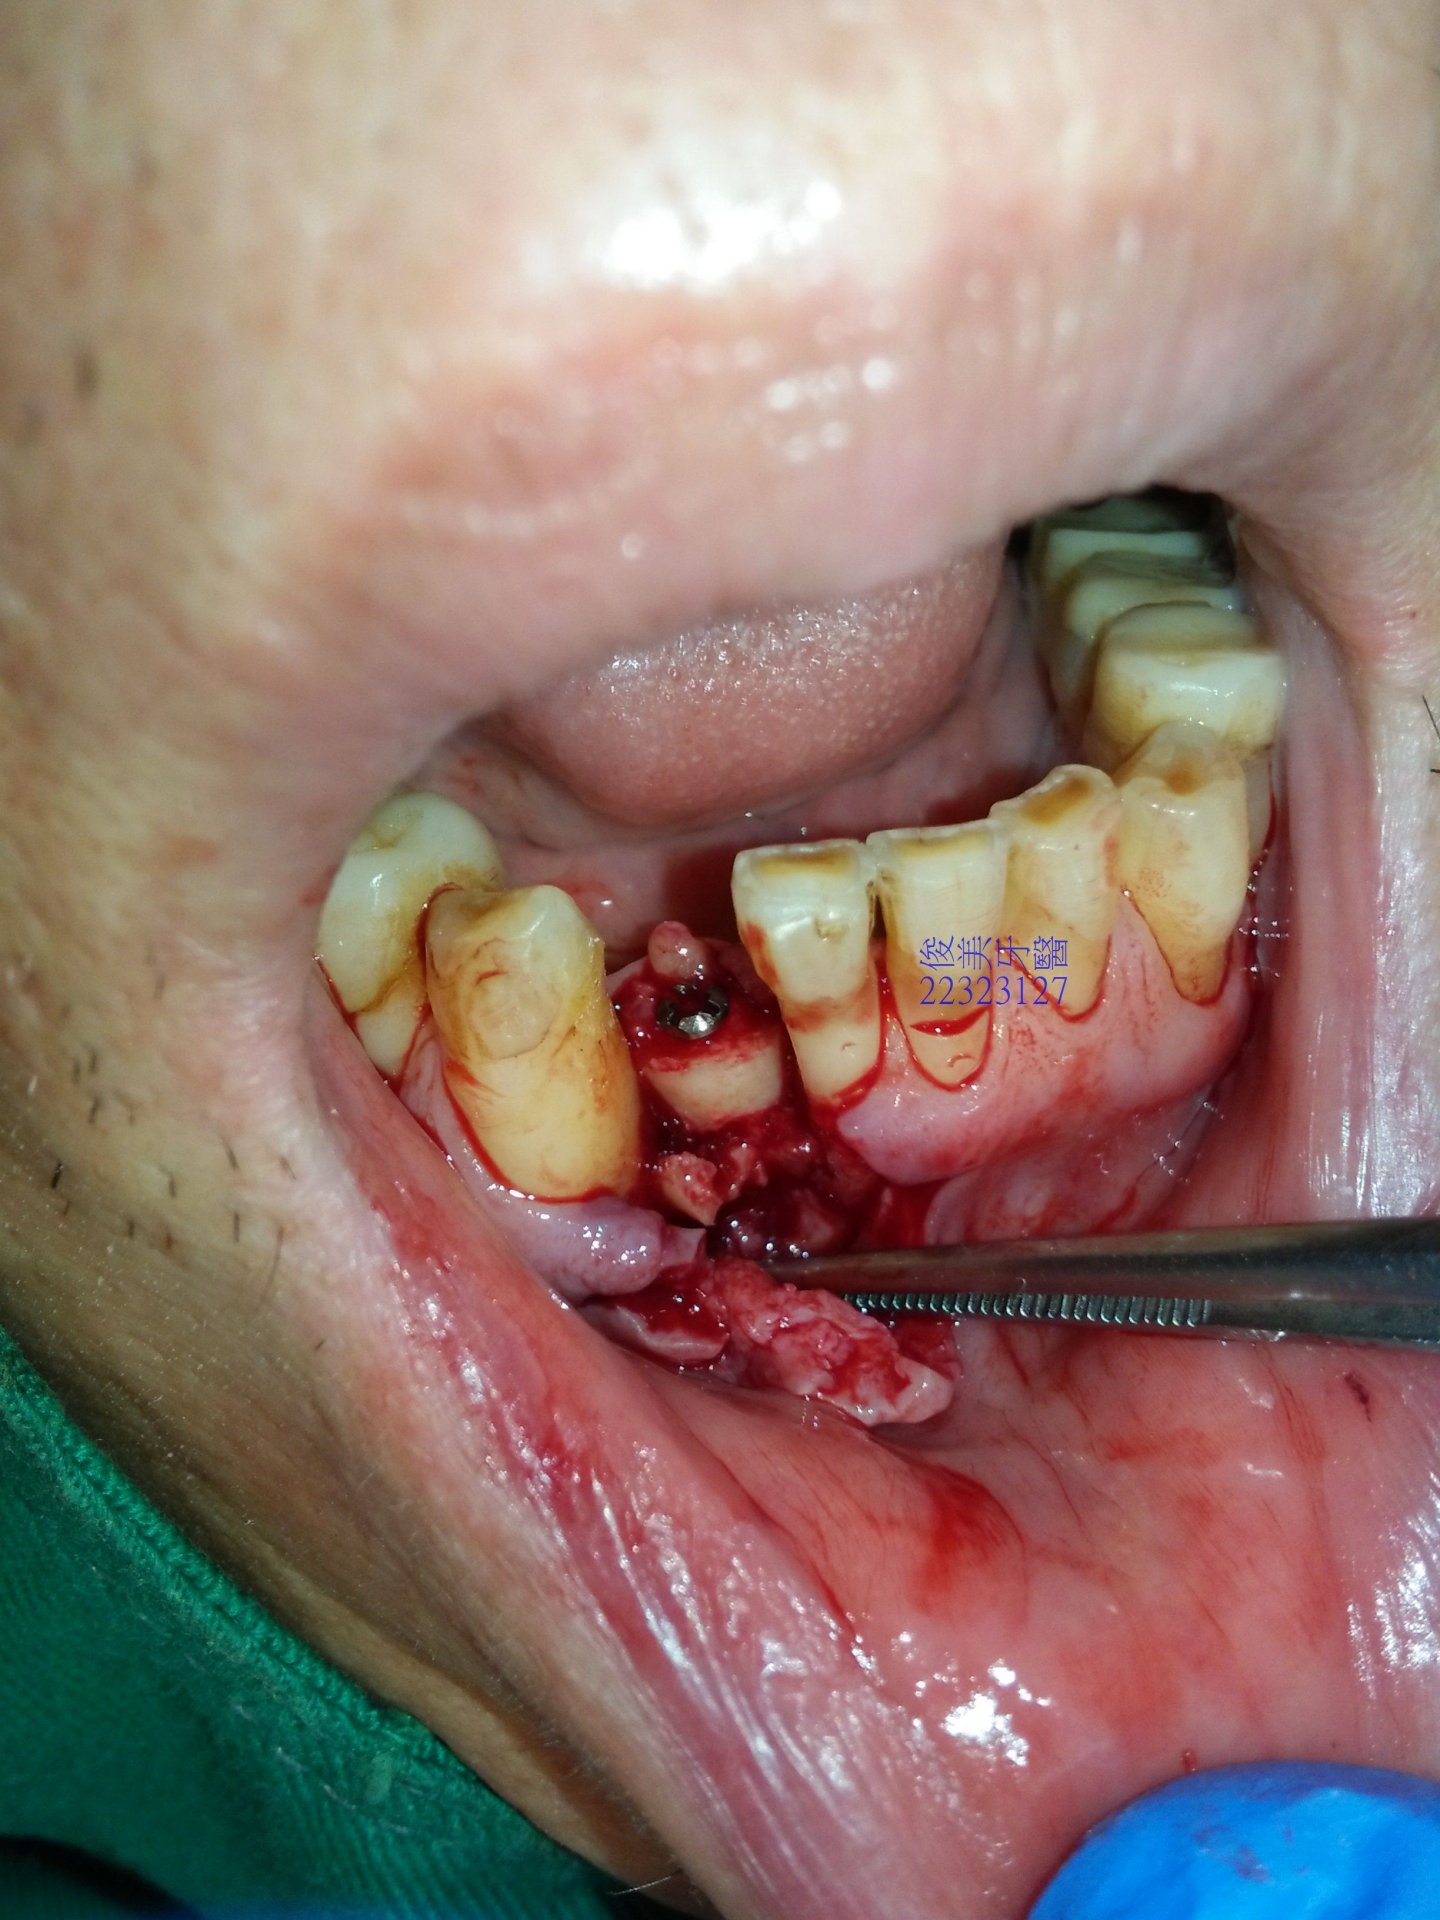

患者骨脊很低,連帶隔壁犬齒的牙根也受到波及,移植骨塊時會一併保護了鄰牙的牙根。

從下顎智齒區取下骨塊,再移植至前牙區,利用特殊骨釘固定,讓自體骨塊癒合、生長。